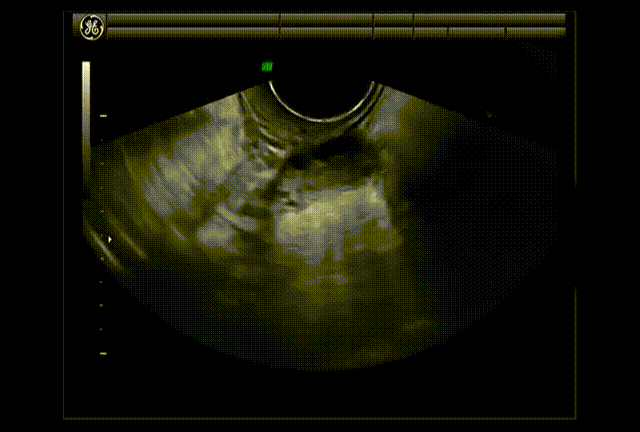

Aspiración Folicular

Una vez desarrollados varios de los folículos y con crecimiento de más de 18 mm, se administra un medicamento para propiciar la ovulación. Entonces la paciente es manejada en un quirófano, bajo sedación o anestesia general, según sea el caso, y se procede a la obtención de los óvulos. A lo largo del tiempo ha ido cambiando la forma de obtener estos óvulos. Inicialmente se hacía mediante cirugía abdominal y viendo directamente los ovarios. Hoy por hoy la mejor técnica es la aspiración endovaginal con guía ultrasonográfifica transvaginal con una aguja especial conectada a un sistema de aspiración. Ingresa el transductor ultrasonográfico con una guía metálica para la aguja a la pared vaginal, previo aseo vaginal, y con la aguja se punciona la pared vaginal a fin de llegar a los ovarios y a cada uno de los folículos para puncionarlos y aspirarlos, y al mismo tiempo obtener al óvulo que contienen.